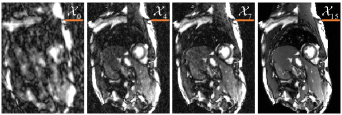

Fig.8 shows the reconstruction results from the iteration modules, where 𝒳0subscript𝒳0\mathcal{X}_{0} is the input aliased image and the other 𝒳isubscript𝒳𝑖\mathcal{X}_{i} related to (22) is the result of the i𝑖ith iteration module. We could find that the first four iteration modules remove the aliasing significantly with the assistance of the transformed tensor low-rank prior from the information that Fig.7 gives and the reconstruction performance of 𝒳4subscript𝒳4\mathcal{X}_{4} w.r.t. 𝒳0subscript𝒳0\mathcal{X}_{0}; the middle modules further preserve the edges and the texture details comparing 𝒳7subscript𝒳7\mathcal{X}_{7} with 𝒳4subscript𝒳4\mathcal{X}_{4}; the last eight modules adaptively suppress the noise and smooth the tissues via the flexible learning CNN from the difference between 𝒳15subscript𝒳15\mathcal{X}_{15} and 𝒳7subscript𝒳7\mathcal{X}_{7}.

Refer to caption

Fig. 8: The reconstruction results from the iteration modules, where 𝒳0subscript𝒳0\mathcal{X}_{0} is the input aliased image and the other 𝒳isubscript𝒳𝑖\mathcal{X}_{i} related to (22) is the result of the i𝑖ith iteration module.